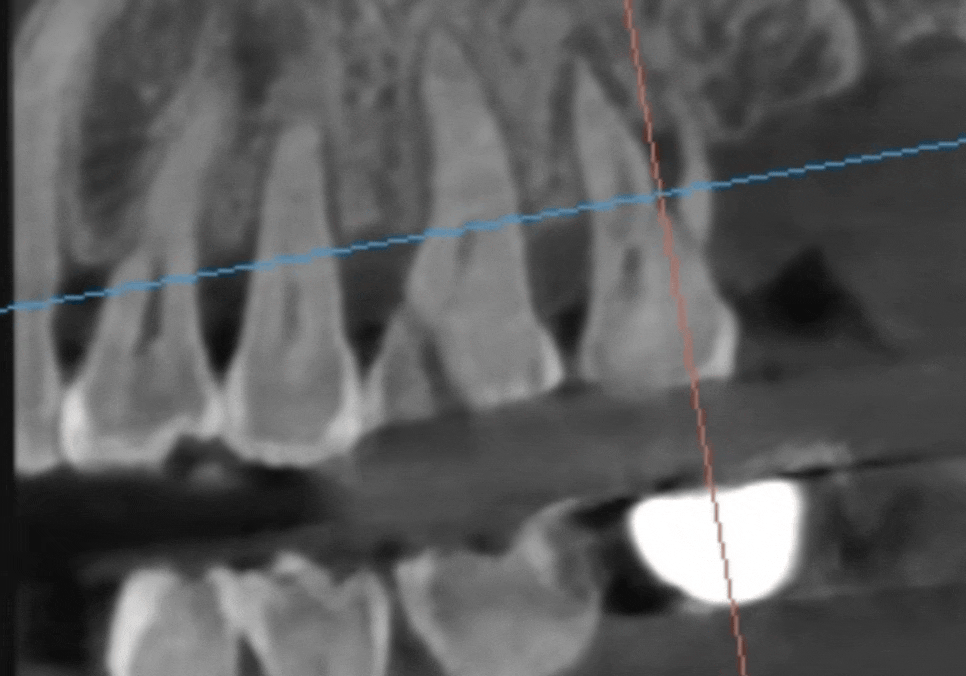

정밀 CT를 통해 분석해 보니,

치아에 금이 가 있는게 보입니다.

250409

앞쪽 어금니(#26)

: 금이 머리 쪽에만 머무른

'치관 파절'로 예후가 좋아 보였지만,

맨 끝 어금니(#27)

: 금이 뿌리 쪽으로 깊게 내려간

'수직 치근 파절' 상태였습니다.